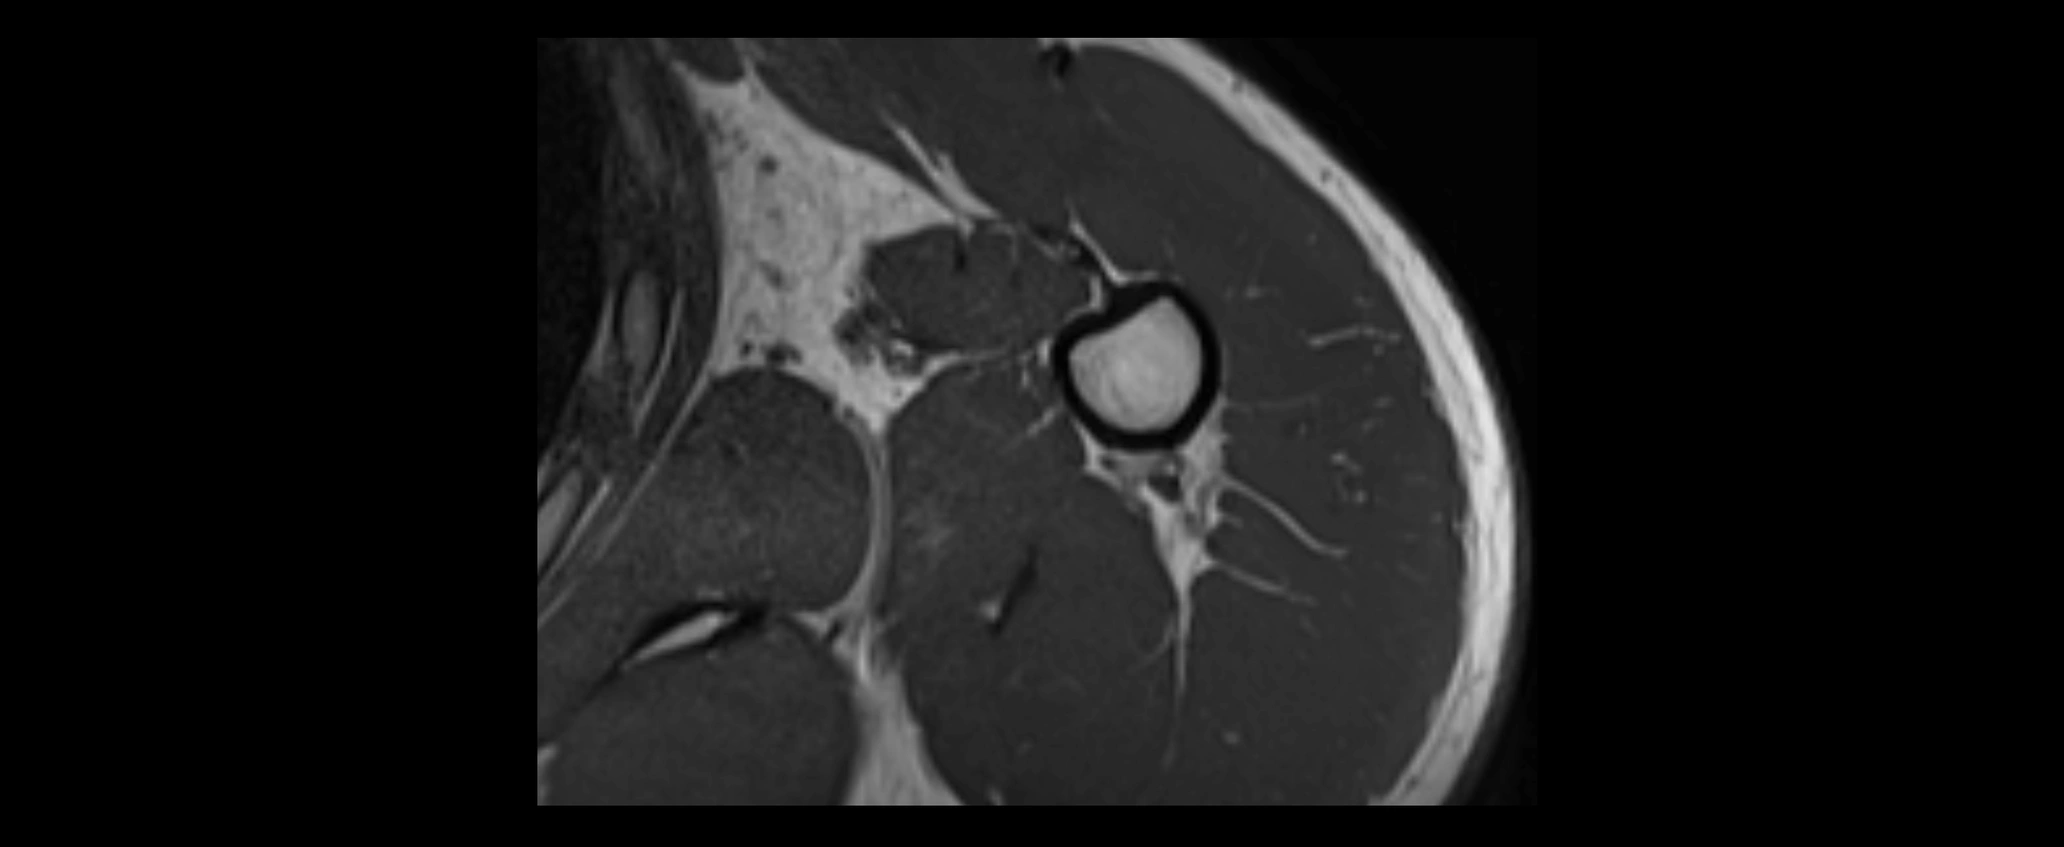

MRI images

image

• STIR:

• Normal ligament: Dark linear band.

• Injury or inflammation: Bright hyperintense signal in and around ligament fibers.

• Highlights periligamentous soft-tissue edema, especially in acute trauma.